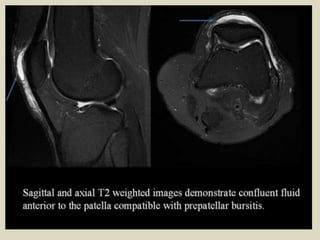

Sagittal magnetic resonance T2 fat sat image showing high-signal

fluid intensity within the prepatellar bursitis.

Axial magnetic resonance T2 fat sat image depicting Baker's cyst with its neck between the

semimembranosus and the medial gastrocnemius tendons. Image also depicts prepatellar bursitis.

Prepatellar bursitis. A 44-year-old female presented with anterior knee pain. Axial (A) and

coronal (B) T2W fat saturated images showing a distended pre patellar bursa (arrows)

Prepatellar bursitis.